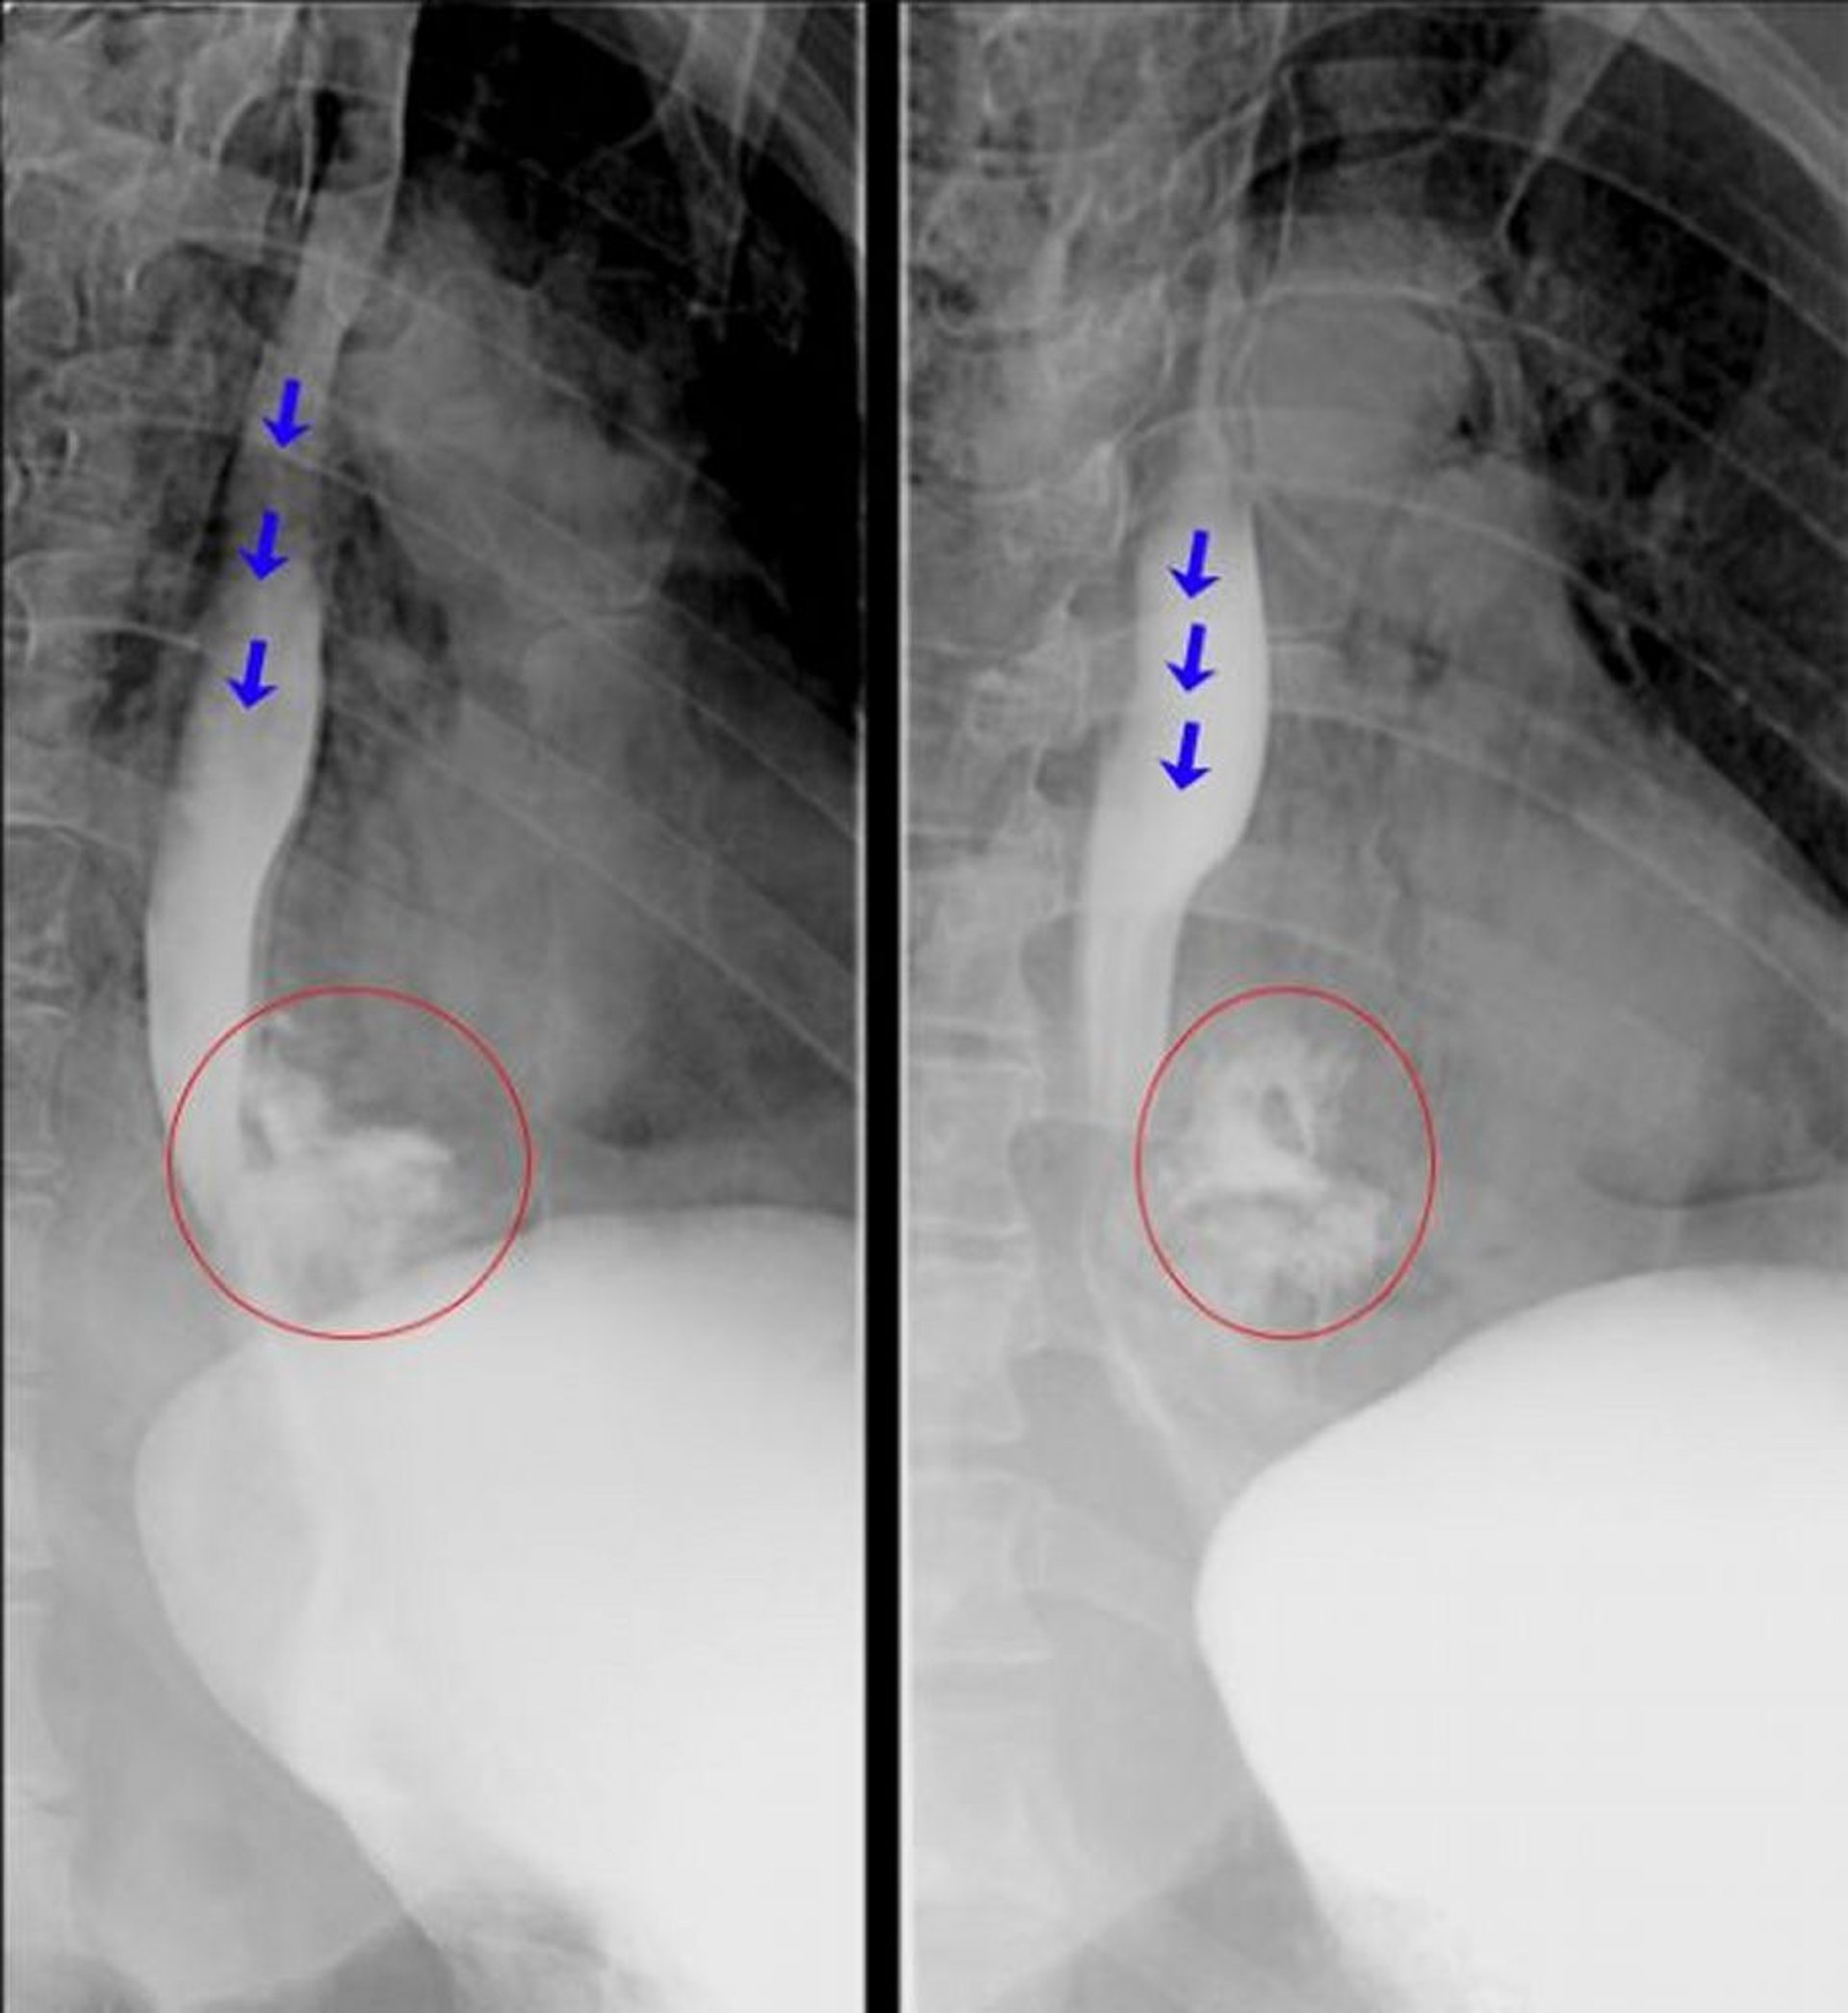

Ösophagographie mit wasserlöslichem Kontrastmittel

Diese fluoroskopischen Ösophagogramme zeigen ein offenes Extravasieren von Kontrastmittel aus dem distalen Ösophagus, was auf eine Ösophagusperforation hindeutet. Die blauen Pfeile markieren das Kontrastmittel im Lumen des Ösophagus. Die roten Kreise markieren Kontrastmittel, das aus der Speiseröhre extravasiert wurde.